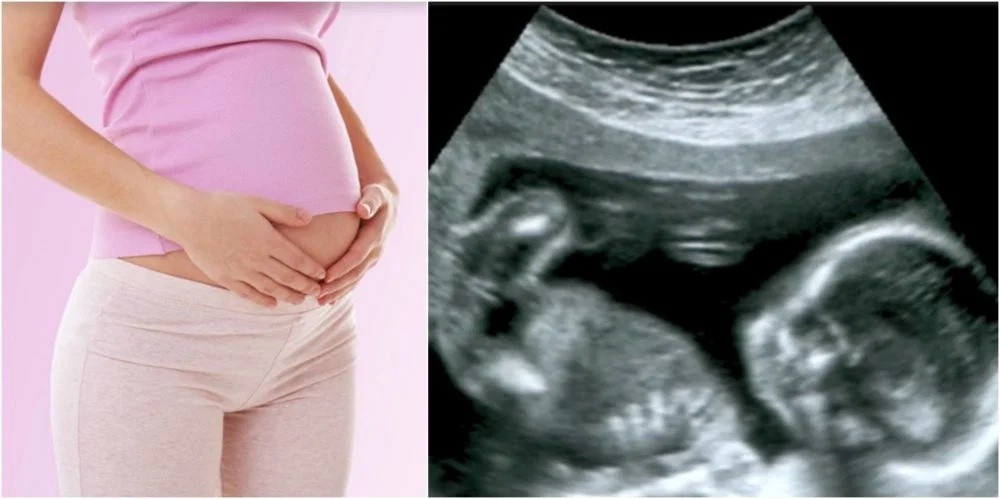

Phạt tiền từ 7.000.000 đồng đến 15.000.000 đồng đối với hành vi bắt mạch hoặc siêu âm hoặc xét nghiệm cho người đang mang thai để chẩn đoán và tiết lộ, cung cấp thông tin về giới tính thai nhì, trừ trường hợp pháp luật có quy định khác. Đồng thời, tước quyền sử dụng giấy phép hoạt động, giấy phép hoặc chứng chỉ hành nghề trong thời hạn từ 1 tháng đến 3 tháng đối với hành vi này.